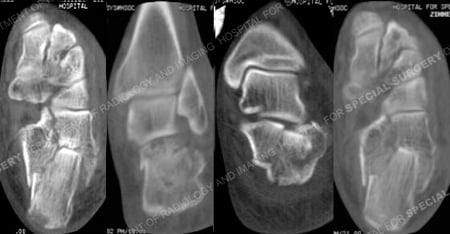

CT scan images further delineating the fracture pattern.

A 68-year-old male was involved in a motor vehicle accident when the car he was driving was struck from behind and pushed into the vehicle in front of him. He was brought to the HSS Orthopedic Trauma Service with complaints of left foot pain and radiographs revealed a left-sided, displaced, intra-articular calcaneus (heel bone) fracture with a depressed articular segment. Fracture surgery was performed by Dr. David L. Helfet using a minimally invasive technique with elevation of the depressed segment, reduction and fixation of the posterior facet and tuberosity including interfragmentary lag screws. He returned at regular follow-up intervals and healed uneventfully, and at 6 months following surgery he presented with good radiographic and clinical results including a healed calcaneus fracture, significant improvement of pain symptoms, and a return to his prior activities of daily living.